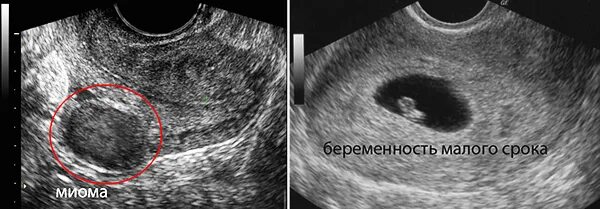

Эндометрий 9 мм